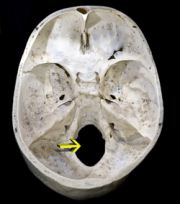

| 20:52, 28 April 2019 | Crane4 Foramen magnum.png (file) |  |

102 KB | Lisa (talk | contribs) | 1 | |